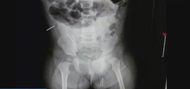

鋼針.jpg

濟南:11個月女嬰...